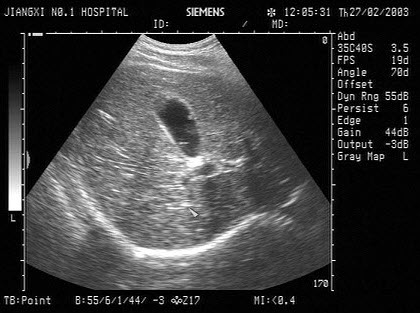

13、单项选择题

女,25岁,因急性胰腺炎禁食5天。声像图如图所示。结合超声声像图,诊断为()

A.胆囊泥沙样结石

B.胆囊内胆汁淤积

C.胆囊多发性息肉

D.胆囊多发性胆固醇结晶

E.胆囊癌